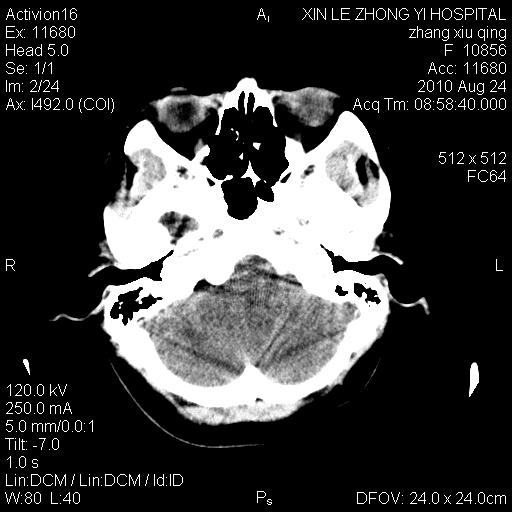

标题: CT28569:看看鞍上池正常吗 [打印本页]

标题: CT28569:看看鞍上池正常吗

女 24 偶有头晕

怎么这么多伪影?我感觉没什么特别异常哦,是不是伪影所至呀

病史?感觉有水肿,炎症或转移

伪影多,建议行mri!